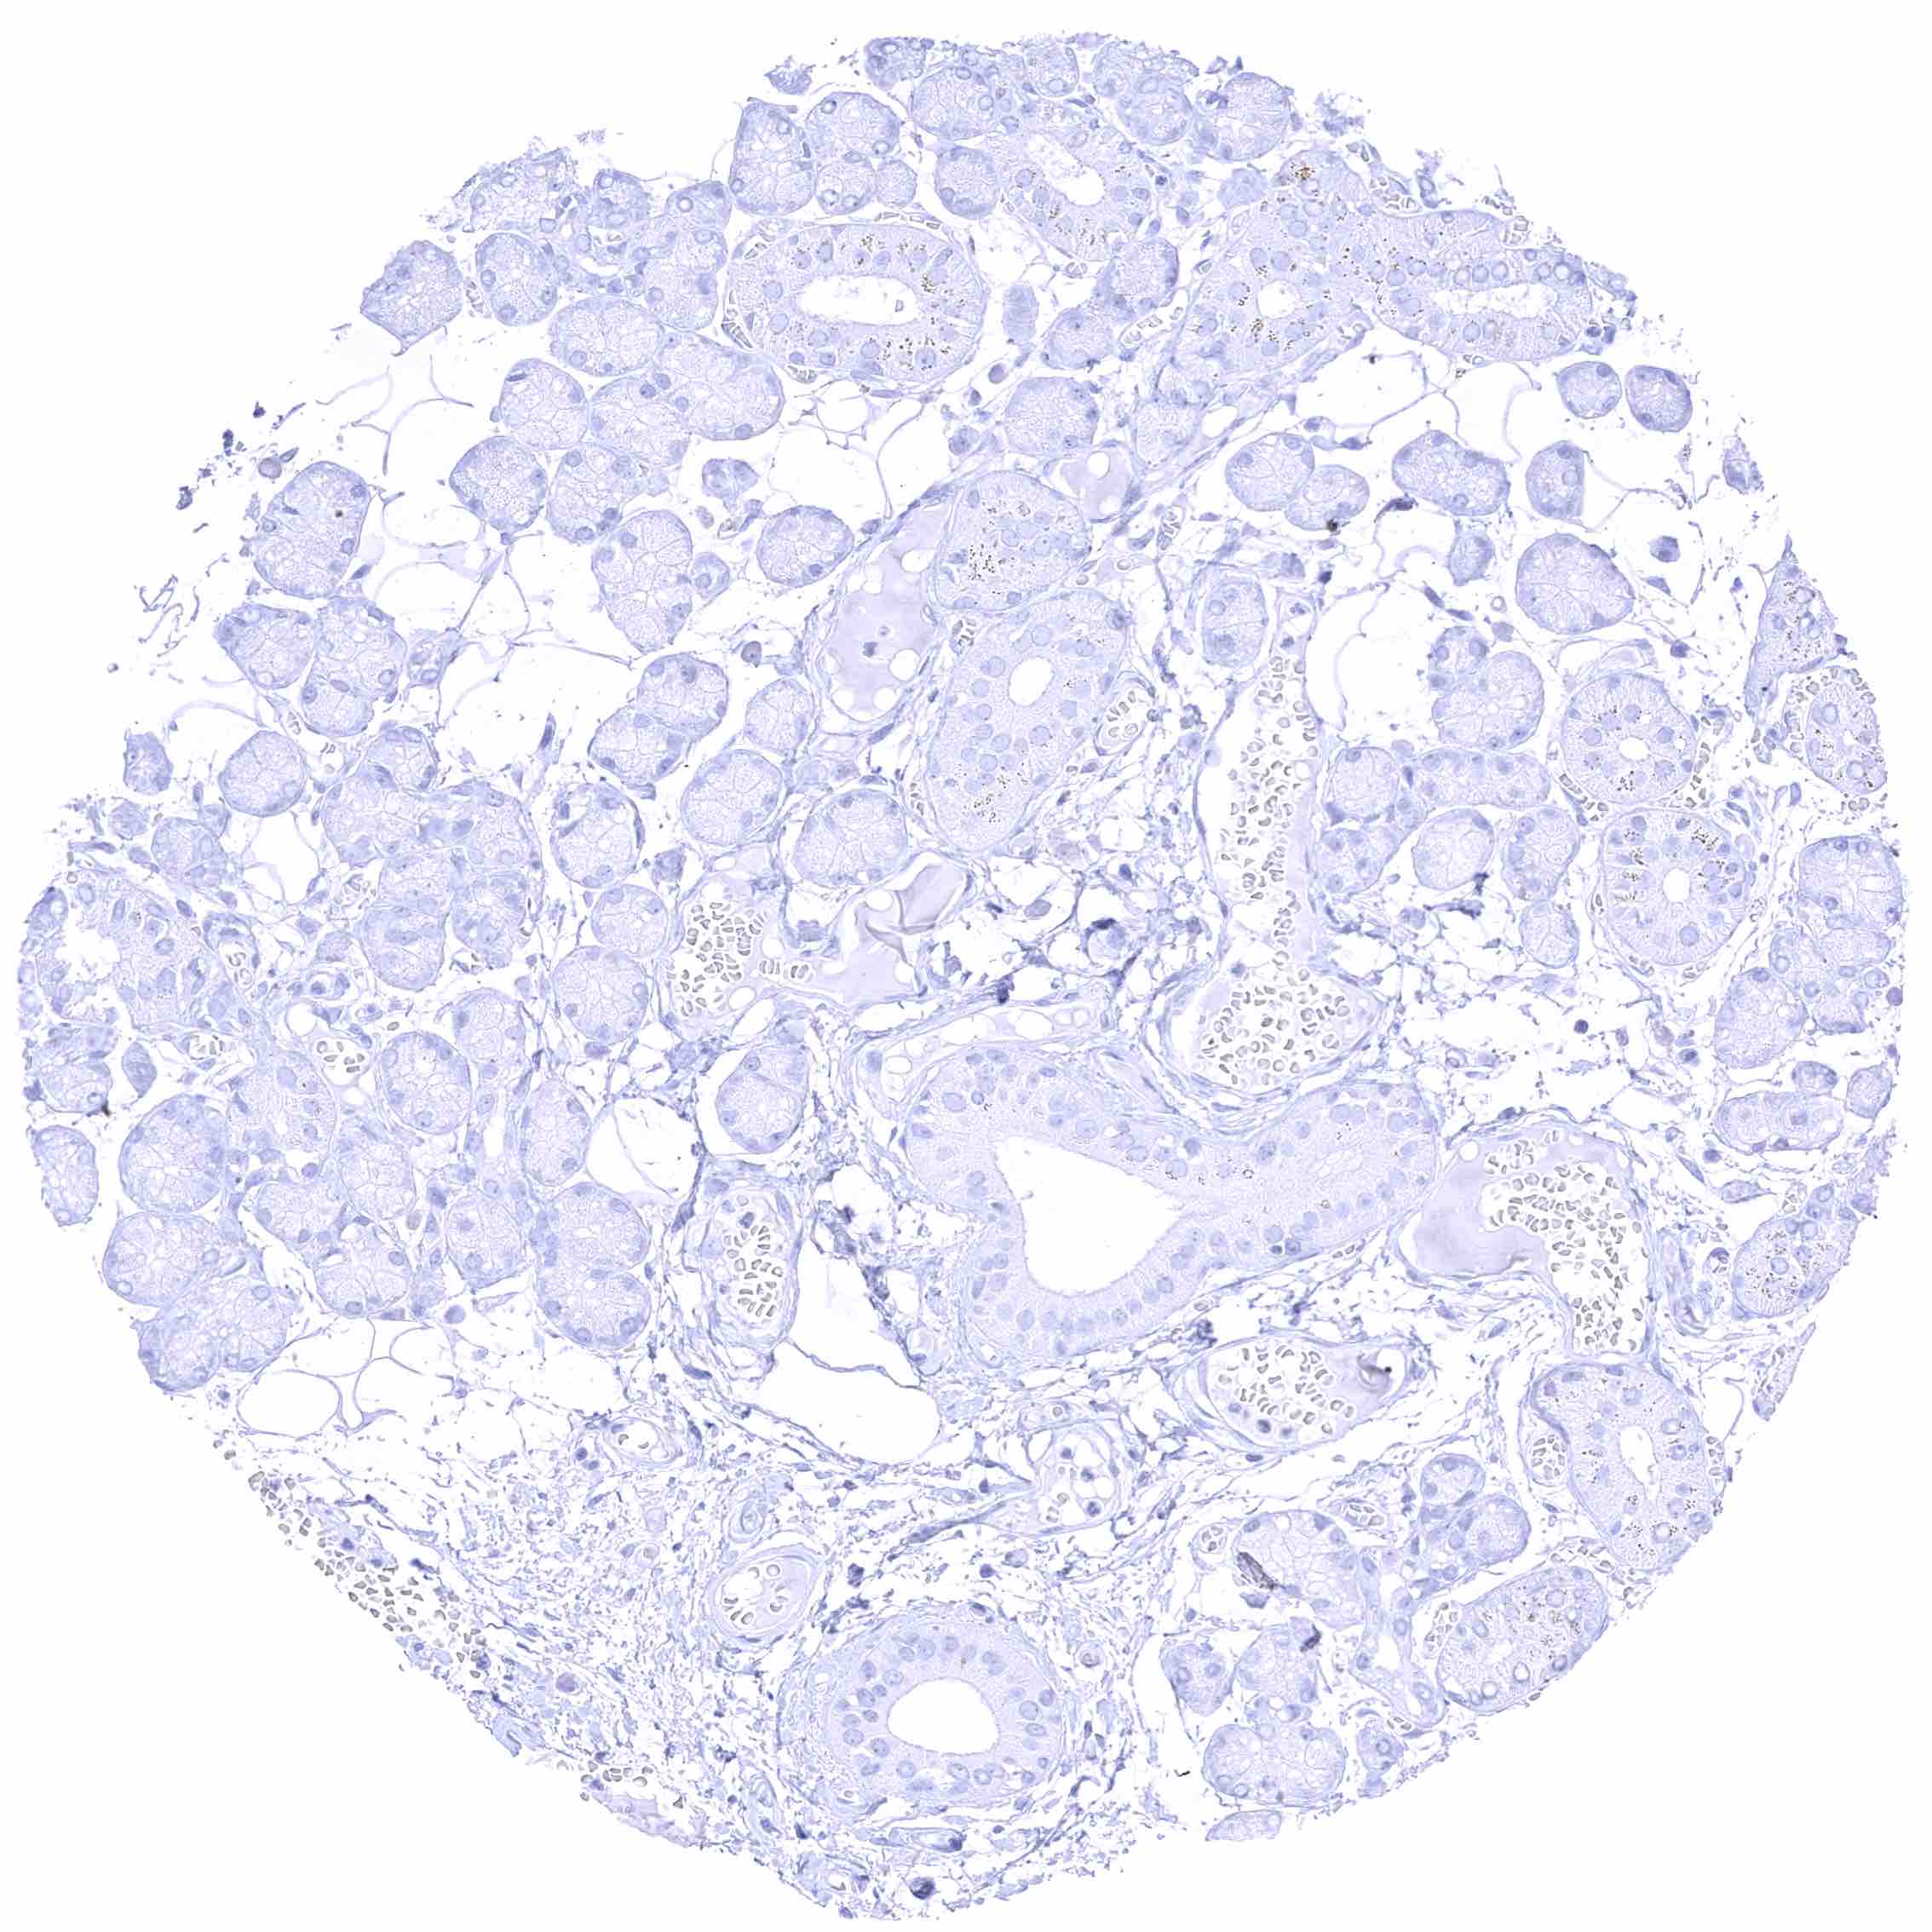

Testis